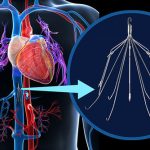

Filtre yerleştirilmesi: Bazen tüm çabalara karşın akciğer embolisini engellemek mümkün olmaz. Tedavi başarısız ise, tedavi başlanamamış yada yarıda kesilmiş ise akciğer emboli riskini azaltmak için toplar damar içine pıhtıları engelleyen bir filtre yerleştirilmesi gerekebilir. Vena kava filtresi

yönteminde kasıktan ya da boyundan kateterlerle en büyük toplar damar olan karındaki vena kava inferiyora yerleştirilir.